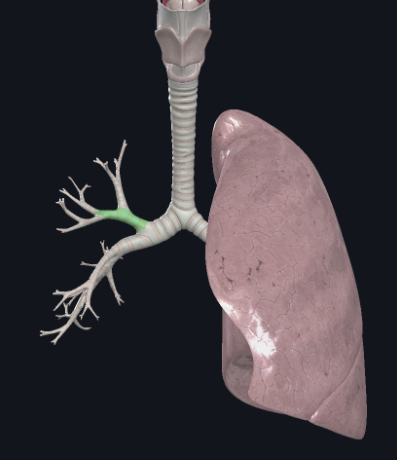

What structure is this?

Right main bronchus

What structure is this?

Left main bronchus

What structure is this?

Left superior lobar bronchus

What structure is this?

Left inferior lobar bronchus

What structure is this?

The carina